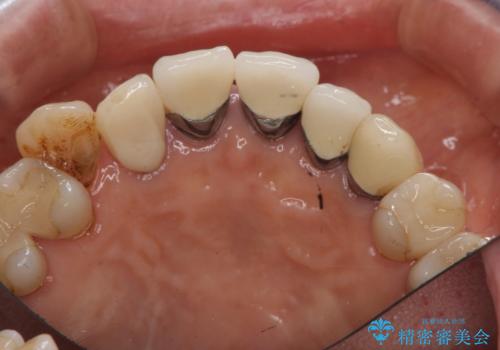

- 他の部位の治療で来院されていましたが、30年以上前に行った前歯のかぶせ物のきわがあっておらず虫歯になってきていました。

神経の治療から念のためやり直ししてからセラミックでかぶせました。

金属の土台が入っていましたがすべて外し、ファイバーコアでやり替えています。